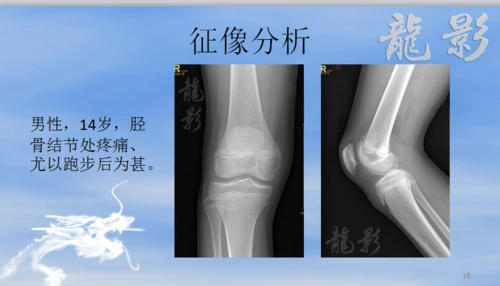

龙影影像公开课——胫骨结节骨软骨炎